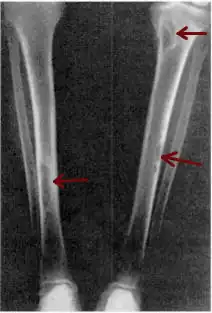

| Osteitis fibrosa cystica of the tibia. Arrows point to the brown tumors which are typically present in bones of people with OFC. | |

X-rays may also be used to diagnose the disease. Usually, these X-rays will show extremely thin bones, which are often bowed or fractured. However, such symptoms are also associated with other bone diseases, such as osteopenia or osteoporosis.[29] Generally, the first bones to show symptoms via X-ray are the fingers.[22] Furthermore, brown tumors, especially when manifested on facial bones, can be misdiagnosed as cancerous.[29] Radiographs distinctly show bone resorption and X-rays of the skull may depict an image often described as "ground glass" or "salt and pepper".[30][31] Dental X-rays may also be abnormal.[2]

Cysts may be lined by osteoclasts and sometimes blood pigments, which lend to the notion of "brown tumors." Such cysts can be identified with nuclear imaging combined with specific tracers, such as sestamibi.[3] Identification of muscular degeneration or lack of reflex can occur through clinical testing of deep tendon reflexes, or via photomotogram (an achilles tendon reflex test).[24][32]

The brown tumors commonly associated with OFC display many of the same characteristics of osteoclasts.[23] These cells are characteristically benign, feature a dense, granular cytoplasm, and a nucleus that tends to be ovular in shape, enclosing comparatively fine chromatin. Nucleoli also tend to be smaller than average.[18]